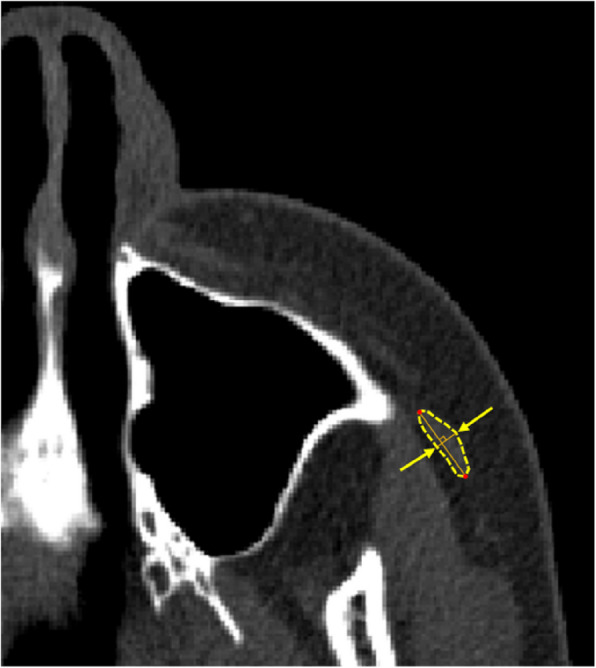

Background: This study evaluated the zygomaticus major muscle and lip-closing force before and after orthognathic surgery. Sixty female patients with jaw deformities who underwent orthognathic surgery were included. Lip-closing force and computed tomography (CT) assessments were conducted preoperatively and 1 year postoperatively. Lip pressure was measured using the Lip De Cum LDC-110R® (Cosmos Instruments Co., Ltd., Tokyo, Japan). CT images were reconstructed using ProPlan CMF (Materialize, Belgium), and zygomaticus major muscle width and CT values were analyzed. To the best of our knowledge, no previous studies have employed CT values to assess muscles in the oral and maxillofacial area.

Results: In both class II and class III females, postoperative zygomaticus major muscle width was significantly higher than preoperative values. In class II females, postoperative zygomaticus major muscle CT values were also significantly higher than preoperative values. Simple linear regression analysis with age as the dependent variable revealed significant associations between pre- and postoperative zygomaticus major muscle widths in both groups. Additionally, simple linear regression analysis with CT values as the dependent variable demonstrated significant associations with postoperative lip-closing force in both class II and class III females.